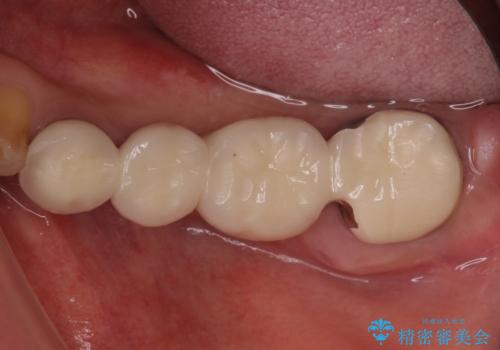

仮歯がない状態を極力避けたいとのことで、外科処置を少しずつ進めていくことになり、治療期間は2年間を要しました。

治療後は痛みなどなく、快適に噛めるようになりました。